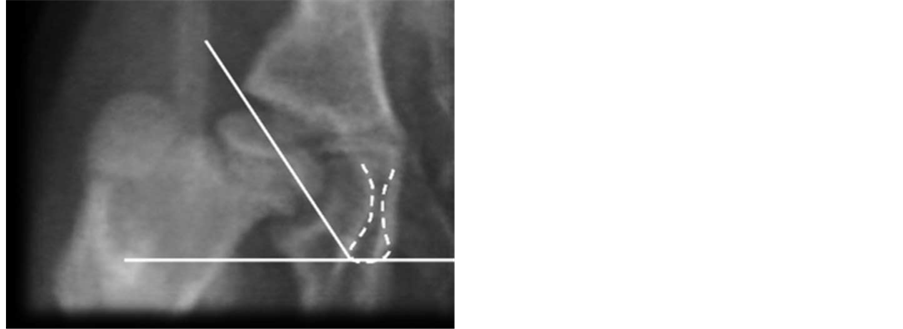

Figure 5. Acetabular depth index (ADI). Acetabulum Deepness is measured by drawing two vectors: the first one from the inferior- external edge until the superior-external of the acetabulum; the second is drawn a vector that is perpendicular to the anterior and that goes until the acetabular background marked by the line (ileopecten) of the iliop- ectineal eminence. It is calculated: p = (b/a) × 100% (n: 60%).

Figure 6. Acetabular antevertion (AA). It’s measured in the true a-p, given by an angle taken from the inferior edge of the acetabulum drawing two vectors which directions are: the first one goes until the medial notch that corresponds to the ending of the anterior wall; the second vector goes until the superior-external edge of the acetabulum (n: 12 degrees). (a) Measured in 3D-CT, (b) Measured in CT scan.